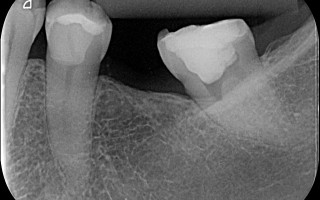

Reintervenção Endodôntica em Molar Superior com Curvatura

Reintervenção Endodôntica em Molar Superior com Curvaturas apicais em todas as raízes. O caso foi preparado com a hibridização com Reciproc R25 e M2 30, 35, 40 e 45.